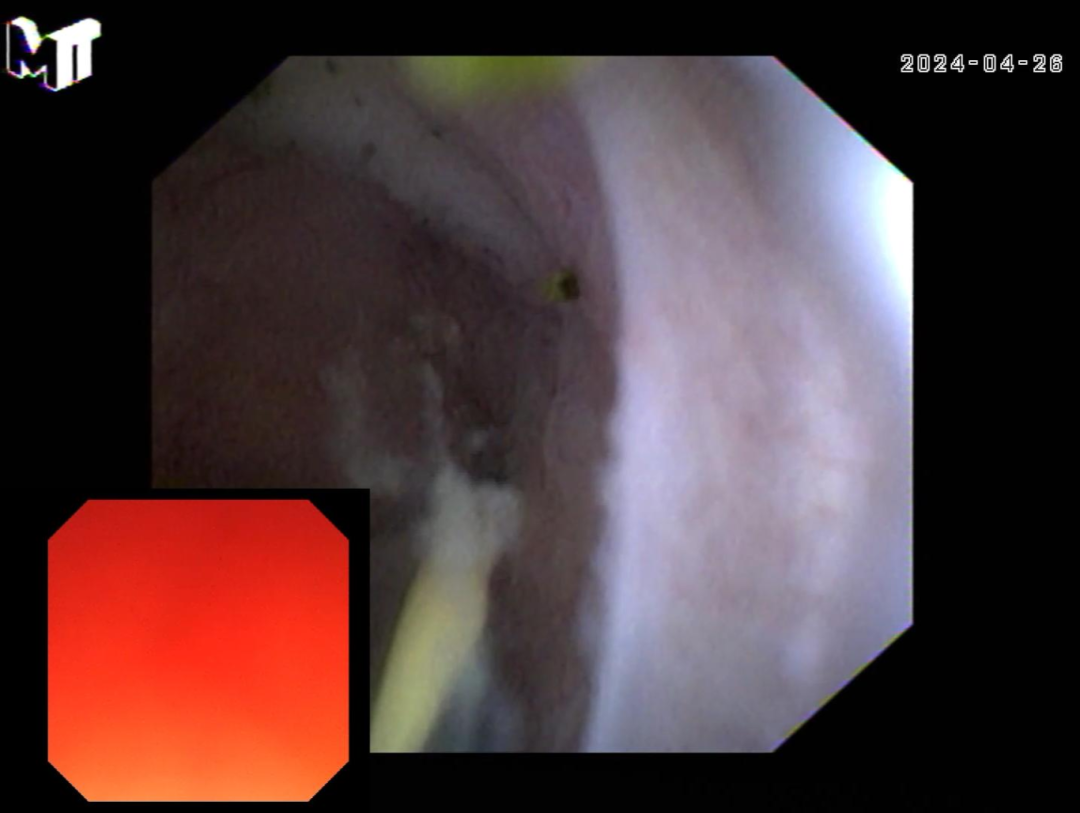

胆囊内部图

新型超细可视导管进入胆囊,不单处理结石,更能直接观察,或许能在不远的将来成为胆囊“切与不切”之间的新标准,为肝胆道疾病患者带来更为精准的诊治方案。 为了更好地为患者服务,我院在临床实践中不断学习、引进、应用新技术,这次新型超细可视导管操作技术的成功开展,标志着我院消化内科检查治疗技术迈上了新台阶。